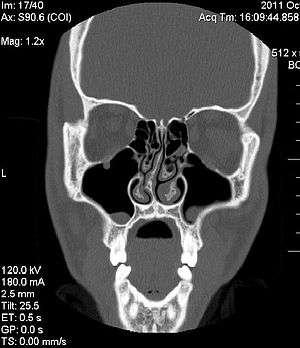

| A CT image showing a congenitally deviated nasal septum | |

Nasal septum deviation or deviated nasal septum (DNS)[1] is a physical disorder of the nose, involving a displacement of the nasal septum. Some displacement is common, affecting 80% of people, most unknowingly.[2]

The nasal septum is the bone and cartilage in the nose that separates the nasal cavity into the two nostrils. The cartilage is called the quadrangular cartilage and the bones comprising the septum include the maxillary crest, vomer and the perpendicular plate of the ethmoid. Normally, the septum lies centrally, and thus the nasal passages are symmetrical.[5] A deviated septum is an abnormal condition in which the top of the cartilaginous ridge leans to the left or the right, causing obstruction of the affected nasal passage. The condition can result in poor drainage of the sinuses. People can also complain of difficulty breathing, headaches, bloody noses, or of sleeping disorders such as snoring or sleep apnea.[5]

It is common for nasal septa to depart from the exact centerline; the septum is only considered deviated if the shift is substantial or is adversely affecting the patient.[6] Many people with a deviation are unaware they have it until some pain is produced. By itself, a deviated septum can go undetected for years and thus be without any need for correction.[6]